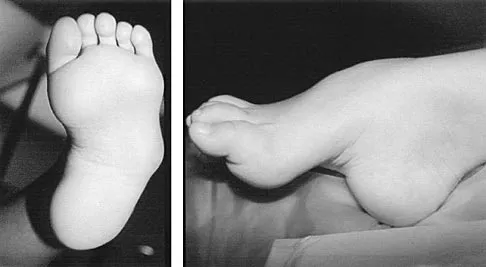

A 2-year-old boy has complete absence of the sacrum and lower lumbar spine. What is the most likely long-term outcome if no spinal pelvic stabilization is performed?

Explanation

Without stabilization, progressive kyphosis will develop between the spine and pelvis. The kyphosis progresses to the point that the child must use his or her hands to support the trunk, and therefore is unable to use his or her hands for other activities. Neck extension contracture does not usually develop. Neurologic deficit, including sexual dysfunction, is generally present at birth and static. Tachdjian MO: The spine: Congenital absence of the sacrum and lumbosacral vertebrae (lumbosacral agenesis), in Wickland EH Jr (ed): Pediatric Orthopaedics, ed 2. Philadelphia, PA, WB Saunders, 1990, vol 3, p 2228.